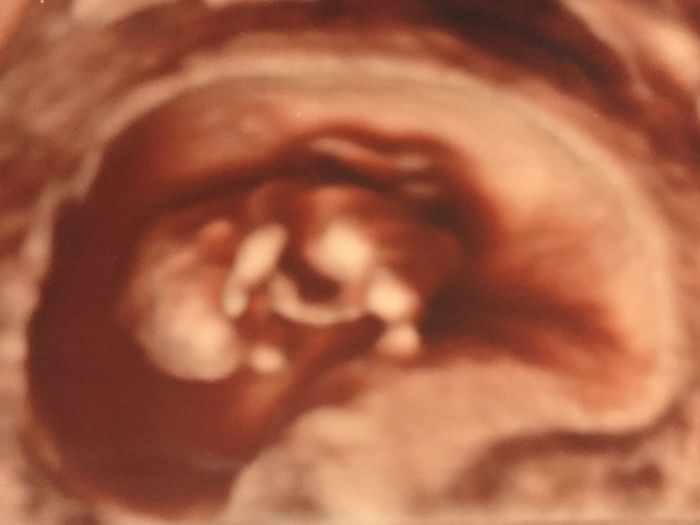

Ahoj maminky :) Tak kontrola je za námi, i odběr krve (5 ampulek), krásný podrobný 3D ultrazvuk, maličké tam tak vesele poskakovalo a točilo se, samé kotrmelce, až jsem se musela smát a pustila i slzu :)) to bylo tak krásné, vidět toho čilého tvorečka, jak tam tančí :D dnes jsem 10+4. Přikládám vám i obrázek našeho malého pokladu :) krásný víkend všem!

Já vůbec nevím Andry :) pan doktor o screeningu vůbec nemluvil, rovnou tam dal 3D, vzal to velmi podrobně, ukazoval prstíky na rukou a páteř, měřil hlavičku, sledoval všechny končetiny...hodně mě to uklidnilo. Všem vám holky přeji, abyste měly také tak nádherný zážitek a jen samé dobré zprávy! A těm, které na své štěstí teprve čekají, ať se brzy zadaří!